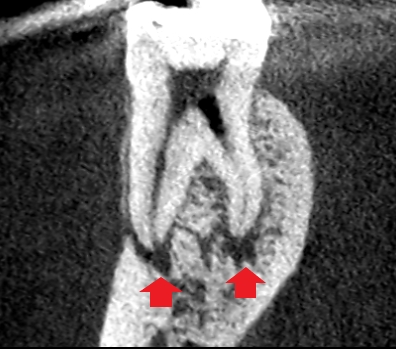

下顎第一大臼歯の初診時の矢状断のCT画像です。

赤い矢印の先に膿の影がみられます。